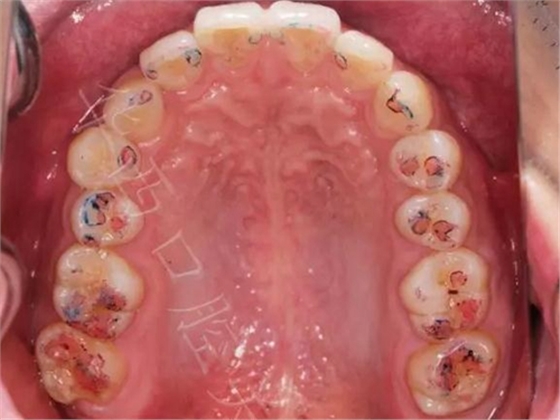

▲ 圖1:100µm咬合紙

▲ 圖2:100µm咬合紙的效果